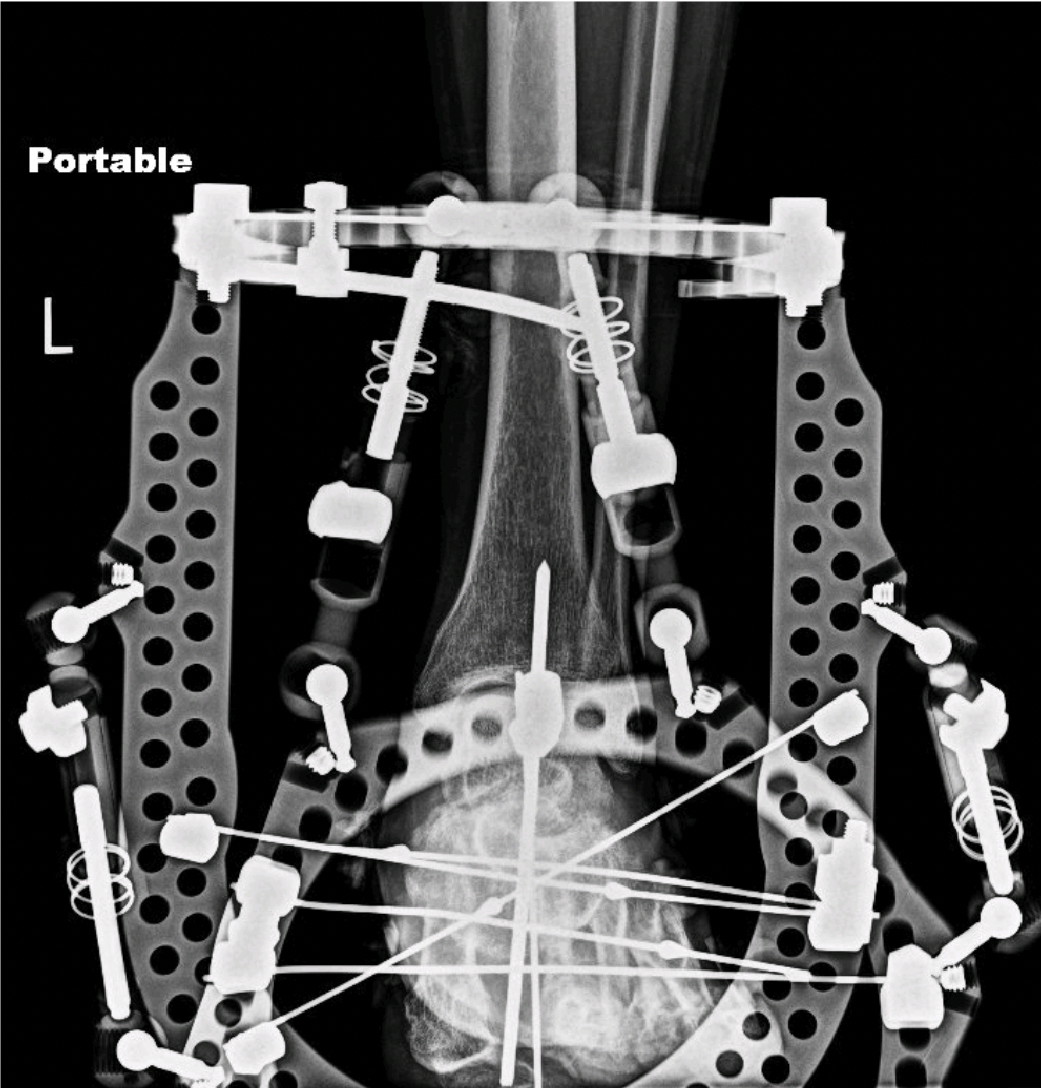

Plain radiographs of the foot revealed advancing destruction and diastasis across the tarsometatarsal joint complex and subluxation of the midtarsal complex. Given the complexity of the deformity in multiple planes and likely progression to an unbraceable foot, we offered the patient an acute correction. Stage 1 would be through a butted frame with hexapod configuration followed by consideration of intramedullary fixation as a second stage if necessary.

Apply the hexapod frame after restoring the calcaneus from equinus. We typically use skinny wires versus half pins, but this is up to surgeon preference. With all connecting struts loosened, manipulate the reducible foot deformity in all planes. This occasionally demands strategically placed small incisions to relieve bone or joint impediments with release using osteotomes and or elevators. When satisfied with the gross appearance of foot architecture, tighten the struts and obtain intraoperative images to confirm anatomic alignment.

It is now necessary to perform final reads of both acute and gradual strut alignment numbers. If these numbers remain consistent with preoperative planning, make no changes to the established deformity correction prescription. If identified changes result from acute corrections performed during the surgery, enter these numbers into the program and develop an updated prescription. Our experience has shown that acute correction mitigates significant postsurgical gradual deformity correction. Regardless, once achieving full correction, osseous consolidation is then permitted. Commonly, our patients remain in these frames for at least 6 weeks and up to 12 weeks. In this recovery time, we determine, based on clinical and radiographic findings, whether the patient will proceed to a staged internal fixation or move directly to extremity bracing.